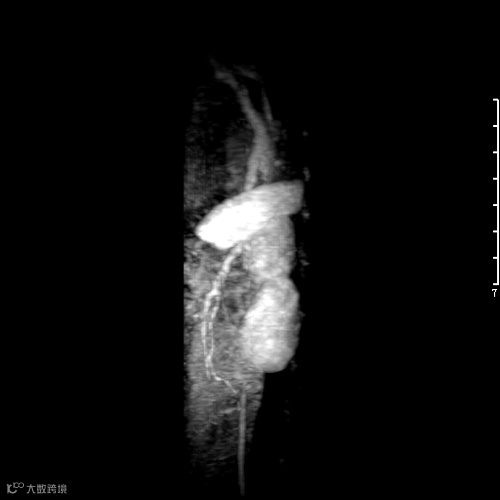

聚多巴氨基酸的儿茶酚基与三价铁离子形成稳定配位结构,在水溶液中自组装成螯合三价铁的聚氨基酸胶束,成功实现磁共振成像(MRI),比商用钆试剂具有更好的弛豫速率(r1=5.6mM−1s−1)。该胶束直接应用于小鼠和兔子体内,成功实现了磁共振血管造影,得到静脉和动脉的清晰三维图像。

本工作为直接合成侧链带儿茶酚的聚氨基酸提供了新的合成方法,含三价铁的MRI探针不仅在影像诊断学上有望取代传统钆离子对比剂,而且在肿瘤诊疗一体化方面该体系还可以同时负载化疗药,以实现肿瘤靶向诊疗。